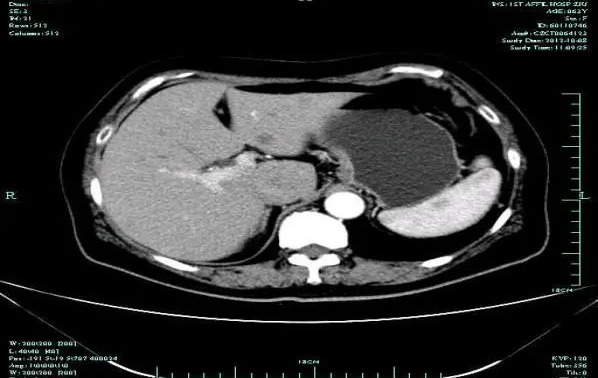

疗效评估:cPR

经院内MDT讨论后:2013.6.13 行“肝转移灶切除+右半结肠切除+胰十二指肠切除+Child重建”

TOGA研究是第一个使用HER2抑制剂曲妥珠单抗治疗不能手术的局部晚期、复发或转移的HER2阳性胃癌患者的Ⅲ期临床研究。TOGA研究结果显示,IHC2+/FISH阳性或者IHC3+的患者与对照组相比,OS分别为16.0个月和11.8个月(HR为0.65)。曲妥珠单抗联合化疗显著提高了HER2阳性晚期转移性胃癌的治疗缓解率和总体生存率。2012年8月,曲妥珠单抗治疗HER2阳性转移性胃癌适应症在我国获批。对该患者进行病理切片会诊,幸运的是其HER2检测为阳性。随即进行靶向联合化疗治疗,三个周期后,肝转移灶消失,曲妥珠单抗治疗效果显著。九个周期的靶向治疗联合放化疗后,疗效评估cPR,随即行手术治疗。